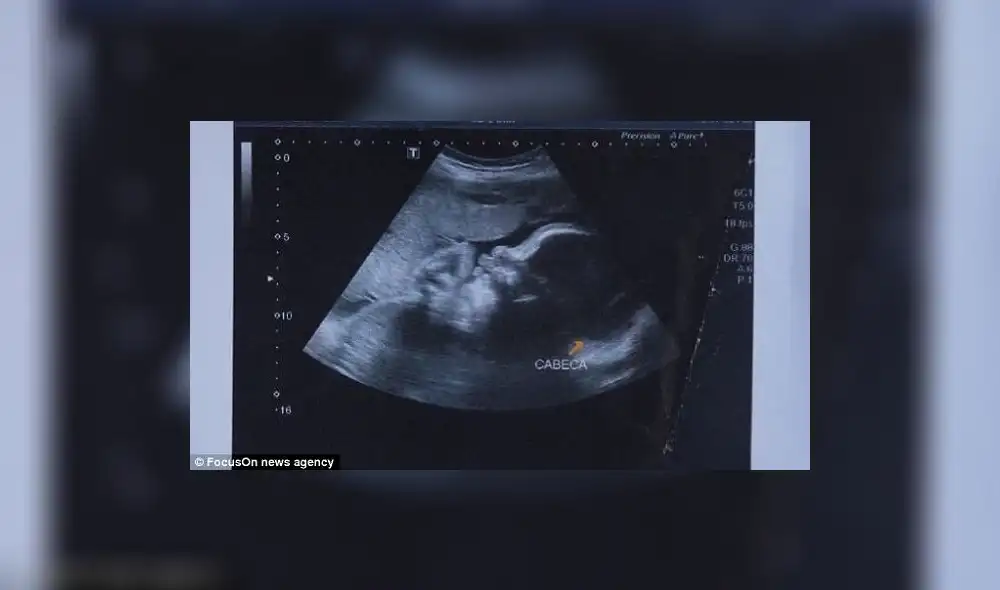

Brasil: Mujer embarazada recibió disparo y la bala impactó al bebé